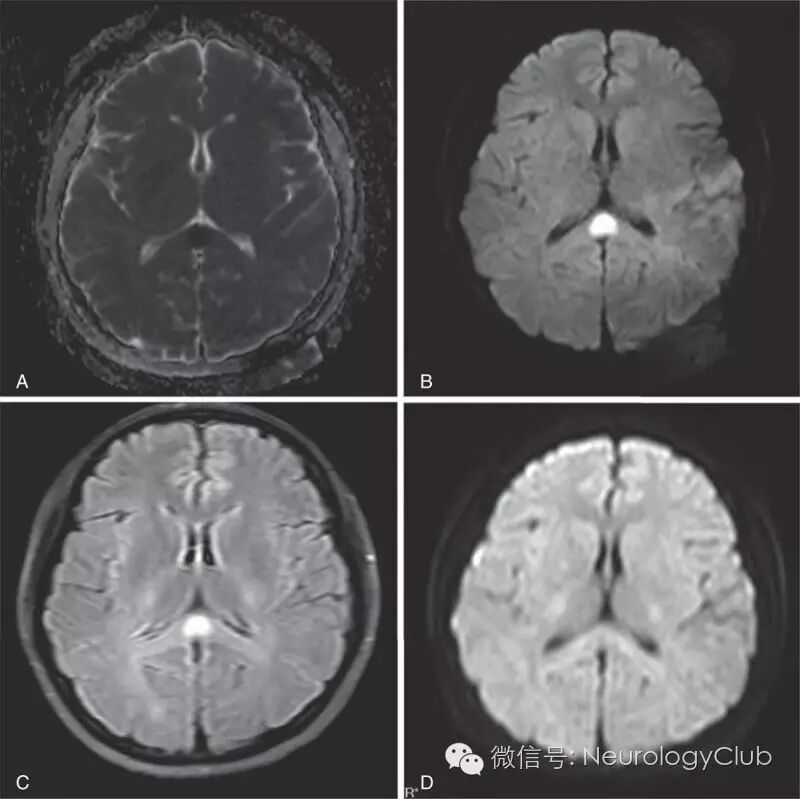

(图2:腮腺炎病毒感染相关的RESLES。起病时的MRI上可见SCC病灶[A-C依次为ADC,DWI和FLAIR],2周后复查病灶消失[D,DWI])